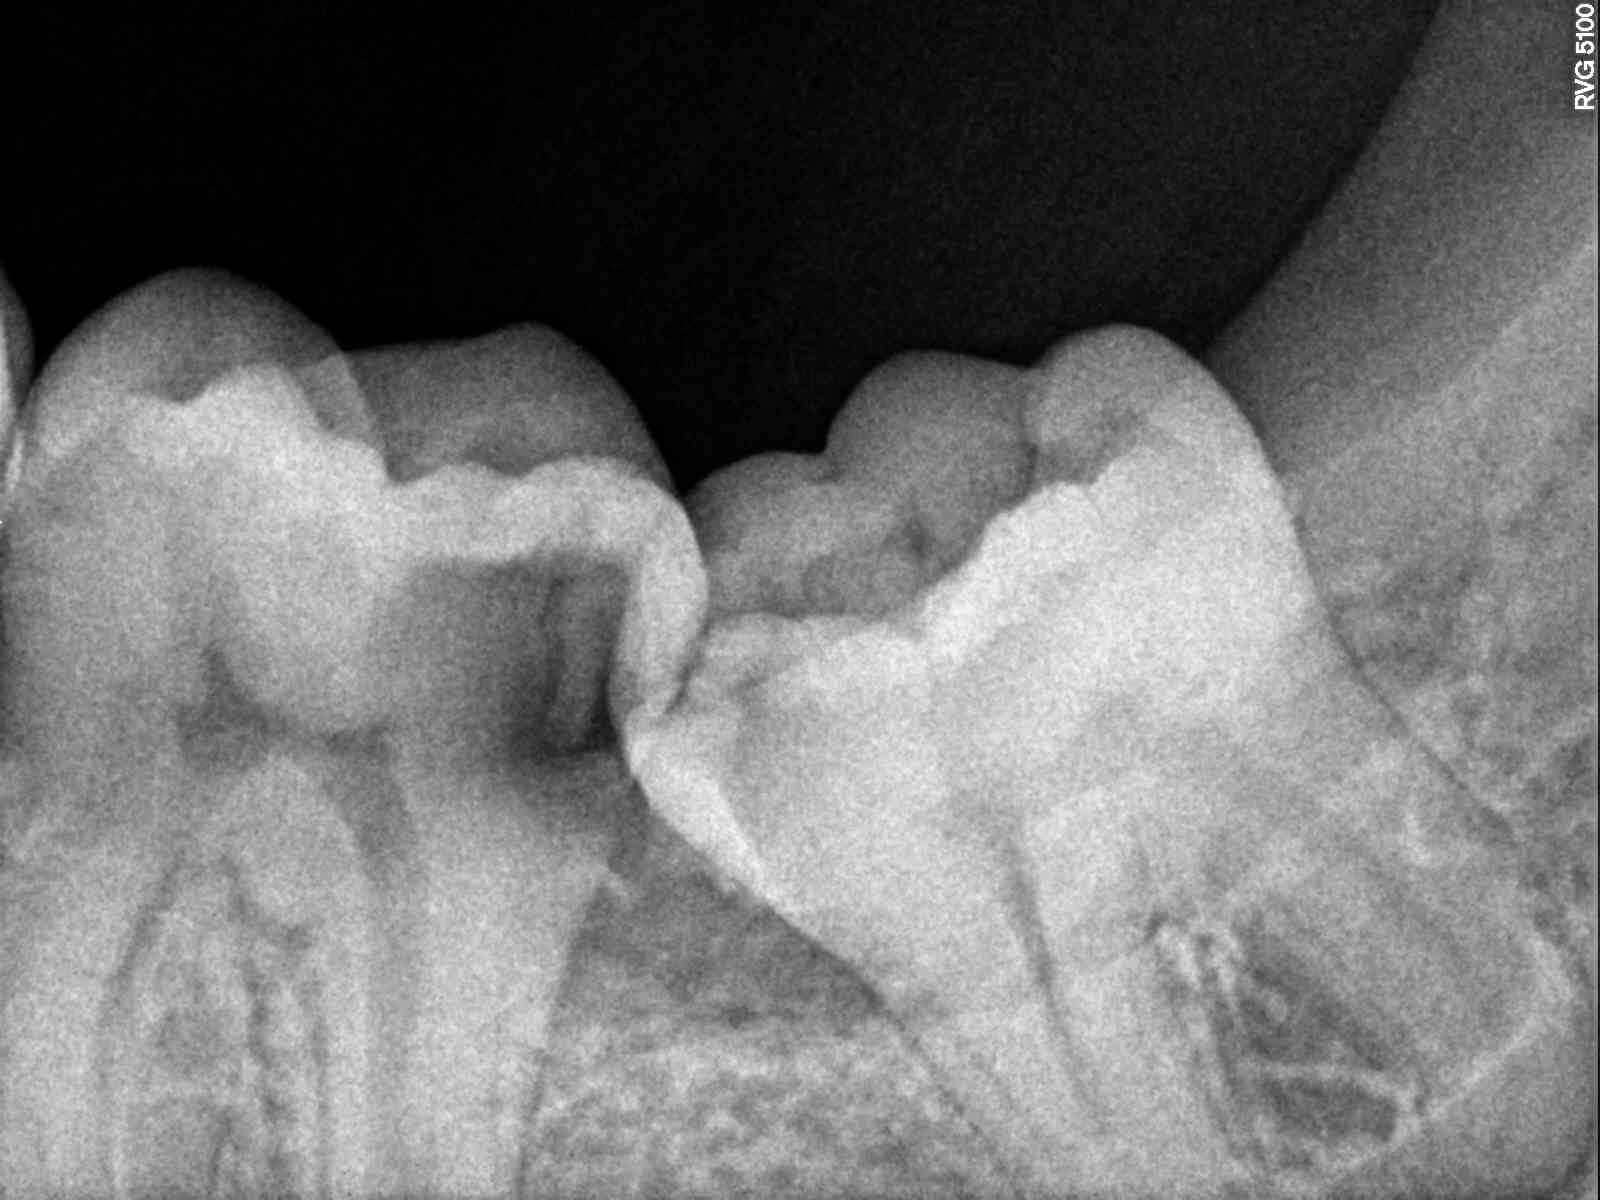

un jeune, 16 ans, retirez-vous les 8 ?

Revoir la reconstruction de la 16 par contre Oui

Elles sortirons enclavées plutôt et le pb c'est pas la DDM future, mais une hygienne complexe et des caries disto-cervicales à coup sûr pour 47 et 37, ça semble déjà débuter sur la pano !

On en voit de plus en plus comme ça, avec des caries difficiles à traiter sur les 7, détecter souvent tardivement, et des couronnes merdiques à réaliser si on veut encore garder les 8...

Si en bouche il n'y a pas de place (la pano n'est pas le seul élément de diagnostic) : à enlever !

pour completer mon Mp, en rebondissant sur le conseil CB de Vernal, cela te permettra de verifier si une resorption de la racine DV des 7 est initiée....j'ai vu une fois une resorption complète sans symptômes à ce stade( découverte radio...)